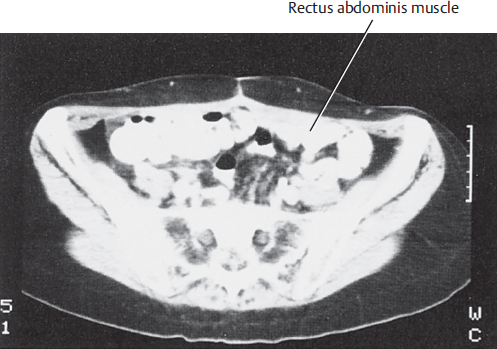

A lower abdominal CT scan at the level of the anterior superior iliac spine illustrates the width of the rectus muscles and the overlying subcutaneous tissue used for the TRAM flap (▶Fig. 50.3).